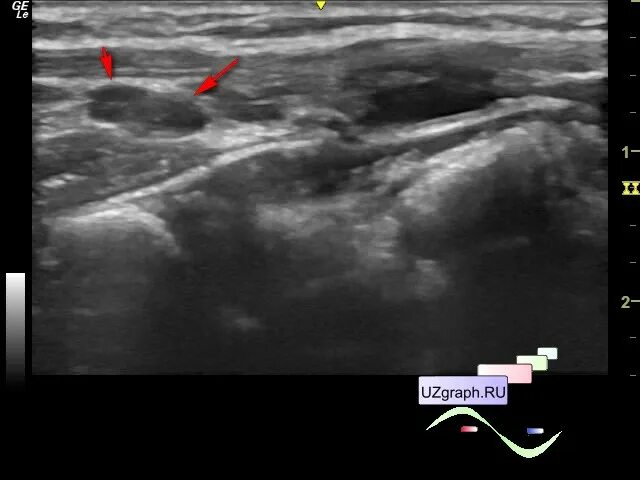

Диффузные изменения щитовидной железы на узи